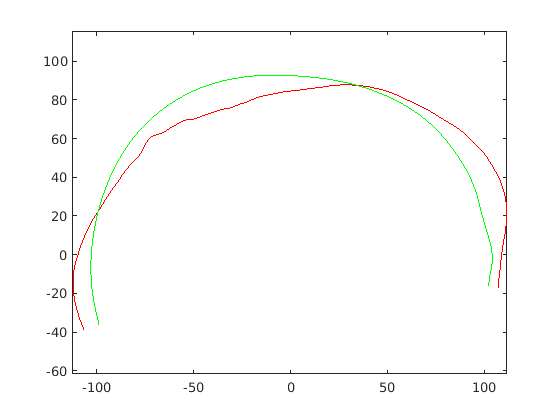

For each of the three segments, we determine the range of gradients on that segment by simple differencing between consecutive points. Each segment is rotated into a 2D frame such that maximum absolute values of positive and negative gradients are equal. Cubic spline contours are fitted to the three profiles and the head profile contour is reconstructed using the three individual cubic splines. Fig. 14 show examples of these.

|

|

|

|